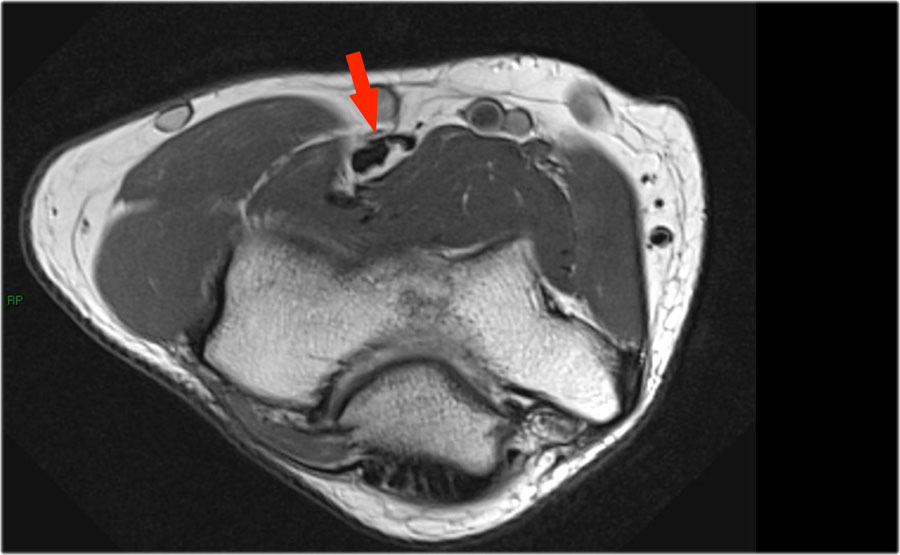

Những hình ảnh này của một nam giới 23 tuổi bị ngã chống tay khi đang trượt ván hai tuần trước.

Khi khám lâm sàng, ghi nhận giảm biên độ vận động khớp khuỷu và đau khi ấn dọc theo mặt ngoài.

Cấu trúc nào nằm phía sau chỏm quay trên hình ảnh cắt ngang?

Sagittal view:

- Một lần nữa, hình ảnh đặc trưng của phù tủy xương thường gặp trong trật khớp khuỷu tay ra sau với vết dập ở phía trước của chỏm xương quay (mũi tên đỏ) và ở phía sau của chỏm con xương cánh tay.

- Chỏm quay phải đã va chạm vào phần sau của chỏm con xương cánh tay.

Cấu trúc phía sau chỏm quay là dây chằng vòng.

Nó không đều và dày lên do hậu quả của trật khớp ra sau.